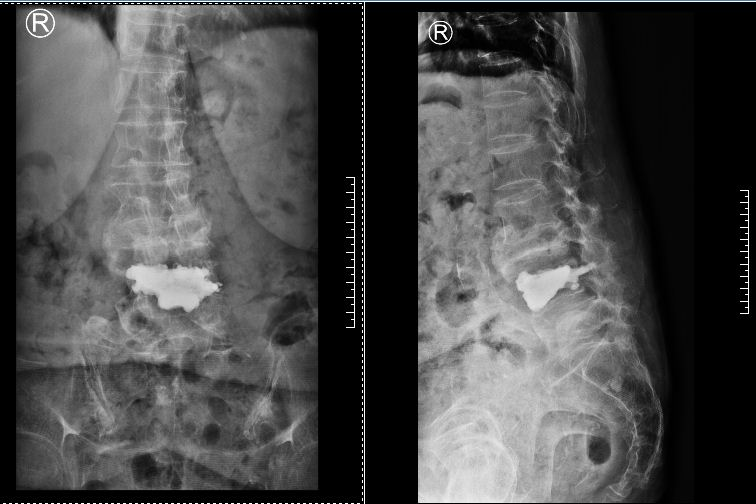

▲张奶奶的三处腰椎骨折(标红处为骨折内巨大空腔、标绿处为陈旧性骨折、标黄处为受压到极限的马尾神经)。

▲术后磁共振、X片